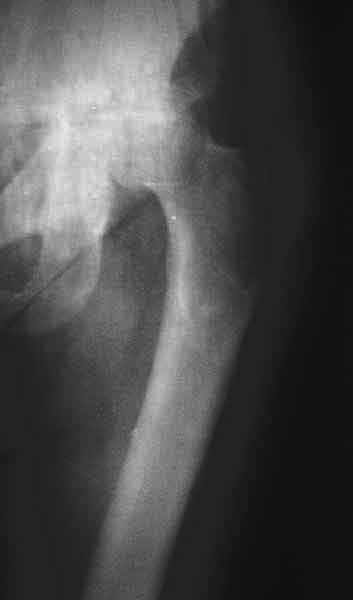

AV> опираясь на стул. На ногу не наступает. Укорочение 8 см. Иногда

А за счет чего такое укорочение? По снимку не видно соответствующего дефекта. Ну плюс приводящая контрактура - но все равно как-то уж больно много. Может, сделать снимки и таза обзорный с обоими проксимальными отделами бедра, и коенный суставов с приложенной линейкой какой?

The X ray that you provided does not show 8 cm of shortening. Perhaps you could send one showing the whole pelvis and proximal femurs.

I agree with Dr Eid's comments. The origin of the 8 cm leg length difference is a puzzle. Is this a clinical measurement? In that case contracture of the joint might affect the measurement. Can we see an AP pelvis to include both hip joints (including a calibration object with a known length) so that the difference in leg lengths that can be ascribed to the hip deformity and bony reabsorption can be measured. This sort of xray will help with templating for the TJR also. I would be very tempted to do a one stage procedure and accept some shortening. Shoe lifts should take care of a 3-4 cm difference.

До травмы проблем с ногой не было. Укорочения, болей и т.п. не отмечал. Сегодня перемерял укорочение - меньше 7 см намерять не

получается :)

По уровню малых вертелов (с учетом рентгеновского увеличения) получается 5 см. Клинически ногу низвести путем тракции невозможно. Из движений - сгибание до 40*, остальные движения "символические".

Ортопедическое укорочение пострадавшей ноги может быть и 7, и 10 см. за счет контрактур в тазобедренном суставе, а вот истинное укорочение, судя по представленным рентгенограммам, вряд ли больше 4 см.